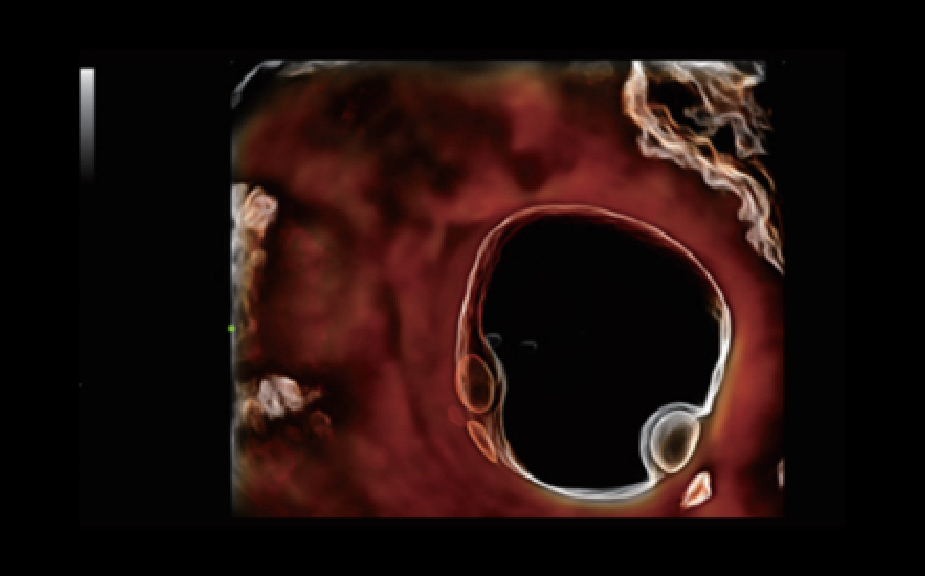

Obrazy kliniczne